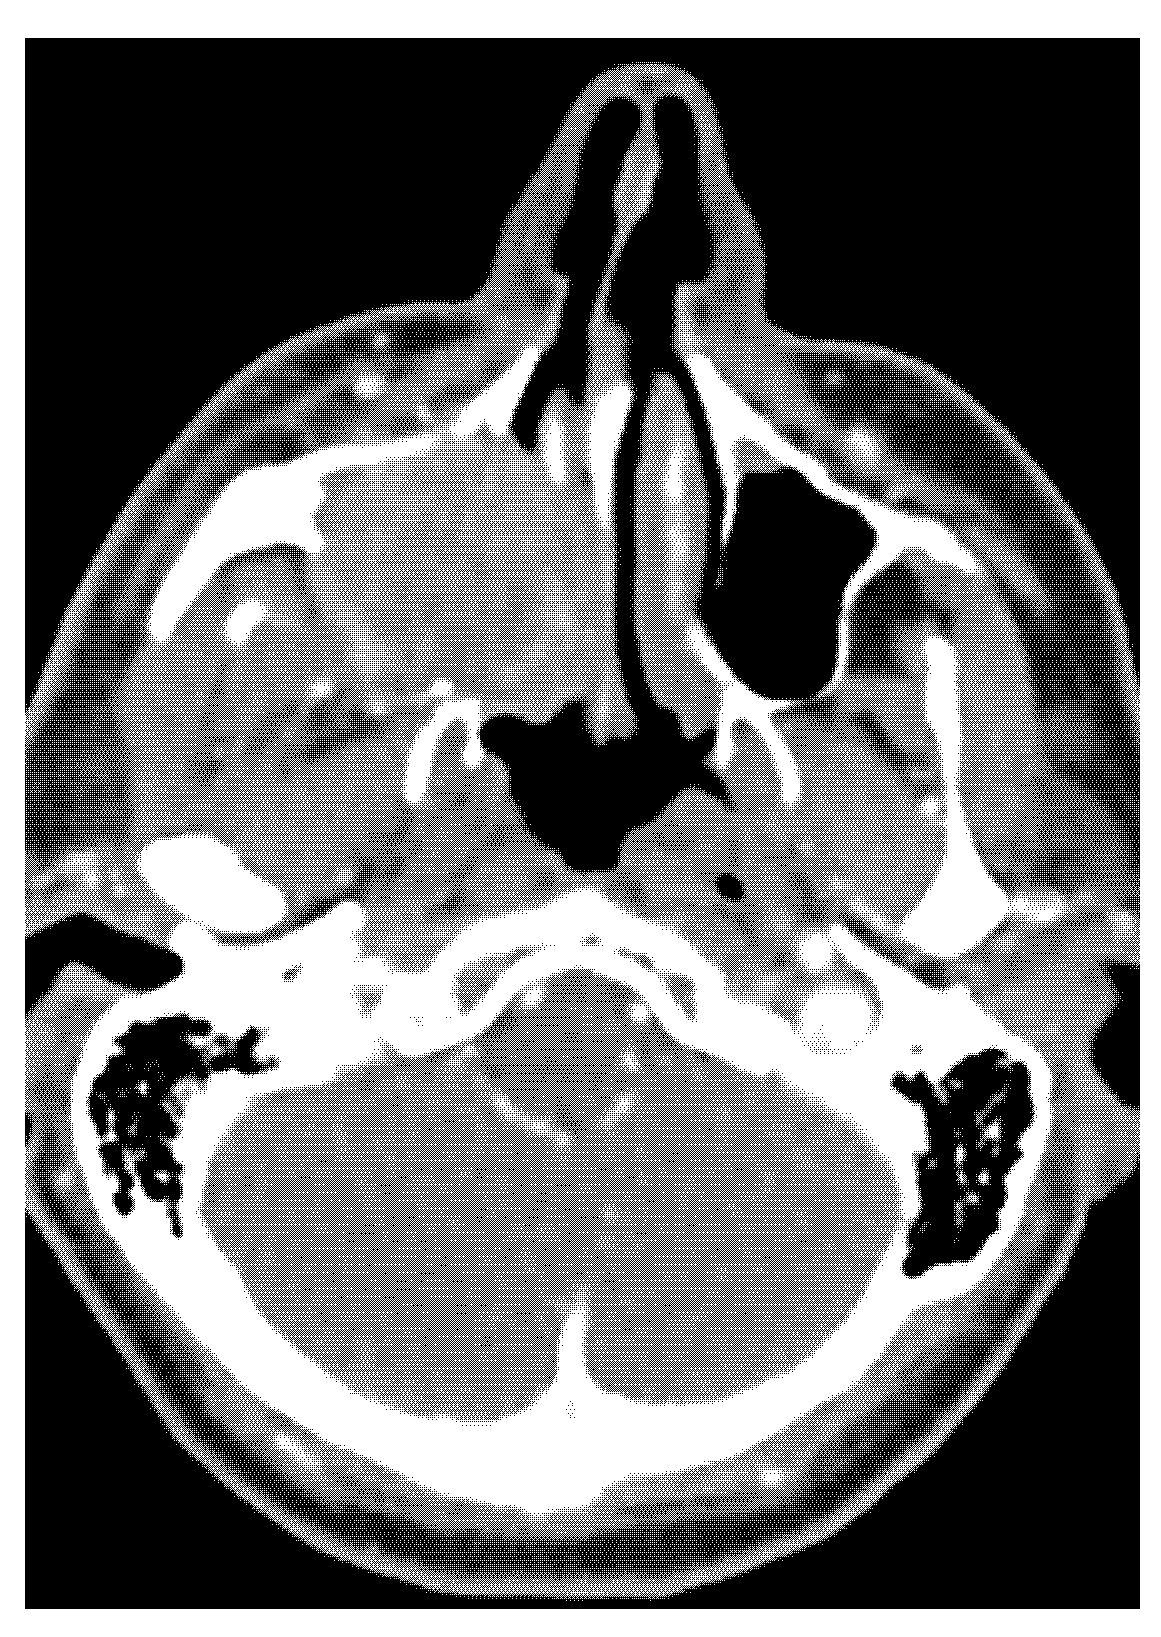

- CT, MRI scan (size, spread, and metastases of tumour mass), if necessary, PET scan, and USG.